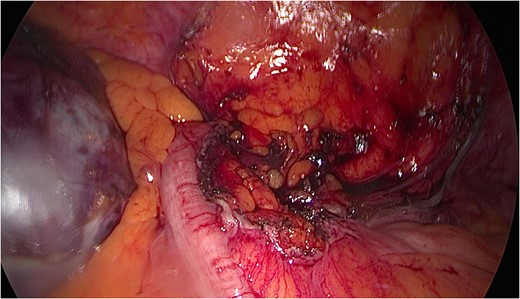

A mesenteric cyst is rare intra-abdominal pathology, with little literature to guide us on how to diagnose and manage it. We report the incident of a 57-year-old female who had an incidental finding of a sigmoid mesenteric cyst whilst undergoing an operation under the care of the Gynaecologists. A computed tomography scan and a flexible sigmoidoscopy followed to help diagnose the lesion as a cyst. A month later the 10 × 15 cm2 cyst was excised laparoscopically with no complications.

The rest of the abdominal cavity was washed with normal saline and closed. Since, the patient has made a full recovery and is completely symptom free. The histology report suggests the mass to be a borderline mucinous cystadenoma with either ovarian or appendiceal origin.

The approach to managing mesenteric cysts vary in the literature. In the acute setting papers have suggested that laparotomy should be the method of choice [8] but more recently there has been a shift to favour a laparoscopic approach [1]. Various laparoscopic techniques have been reported, however, the optimal approach for the best outcome is still unknown due to the rarity of the condition.